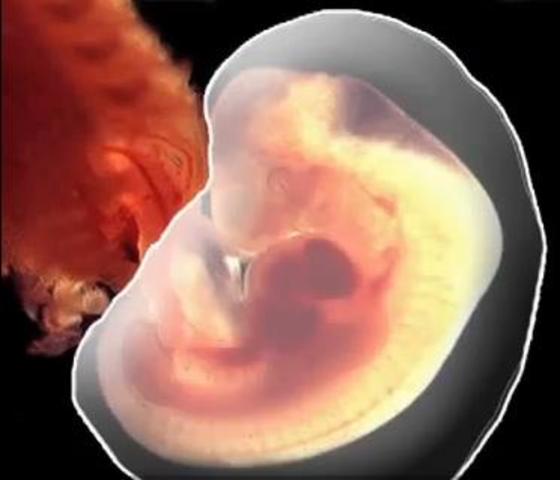

• Disco embrionario trilaminar

Disco embrionario trilaminar

En la 3er semana el embrión mide 2mm. y la forma del futuro embrión sigue siendo un disco ovalado, pero ya posee tres hojas de tejido